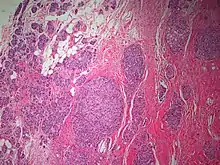

The microscopic histopathology of PACB tumors prepared with hematoxylin and eosin staining shows that >90% of the tumors consist of apocrine gland-like tissue. The lesions must also show that tumor cells have broken through their ducts of origin to invade adjacent tissue in at least one area. Most of the tumor cells (termed type A cells[15]) typically appear somewhat more irregular than normal apocrine gland cells. They have abundant eosinophilic (i.e. pink due to the uptake of the eosin dye) cytoplasm which contain numerous granules[11] and large mitochondria.[15] Their nuclei are large, variably sized and shaped, have multiple nucleoli (which are eosinophilic[11] and may be distinctively large in size[14]), and are surrounded by highly visible nuclear membranes. The cells are arranged into solid sheets, nests, papillae, and/or cords (see Figs. 1 and 2).[11] The tumor cells' cytoplasmic granules test positive when treated with the PAS diastase stain.[16] Binucleated cells, i.e. cells with two nuclei, are common.[10] Less commonly, type B apocrine cells are present; these cells have a more foamy and vacuolated cytoplasm (i.e. containing multiple vacuoles) than type A cells[15] and often resemble foamy histiocytes or sebaceous gland cells.[17] The tumor cells have low to moderate rates of proliferation based on their Ki-67 protein levels.[7] PACB tissues may have localized areas that contain mucin-like secretions within their luminal ducts,[10] localized areas of necrosis (i.e. foci containing dead or dying cells), and/or microcalcifications spotted throughout the apocrine tissue.[11] The stroma (i.e. connective tissue between the sheets, nests, papilla and cords of cells) typically contains non-malignant, infiltrating lymphocytes (see Fig. 3). In an examination of 41 PABC tumors, 33 (80.5%) had <50% of their stroma tissues infiltrated with these cells while 8 (19.5%) had ≥50% of their stroma tissues infiltrated with them. Tumors with ≥50% of their stroma infiltrated with lymphocytes tended to have carcinoma cells that had high rates of proliferation.[11] Metastatic and recurrent PACB tumors have a histopathology similar to their original primary tumors.[14]